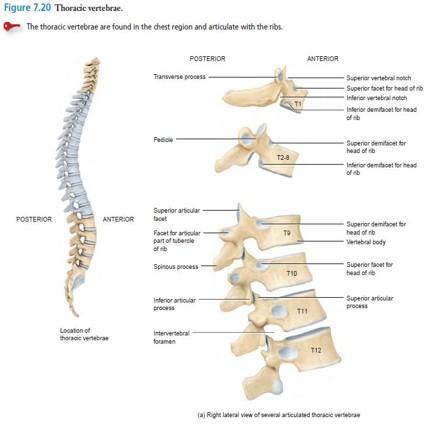

Identify the landmarks thoracic vertebrae 1-12

Spinous process

(SP)?

Transverse process (TP)?

Costal facets along vertebral

bodies (CF)?

Transverse costal facets (TCF)?

study picture

look at picture

what do the costal facets have along the vertebral bodies, except for where?

what is the transverse costal facets along? except for where?

Costal facets along vertebral bodies (CF)...Pairs of inferior (ICF) and superior (SCF) on vertebrae except lower 4 thoracic vertebrae

Transverse costal facets (TCF)..along transverse processes except lower 2 thoracic vertebrae...notice how T12 in pic does have a transverse costal facet